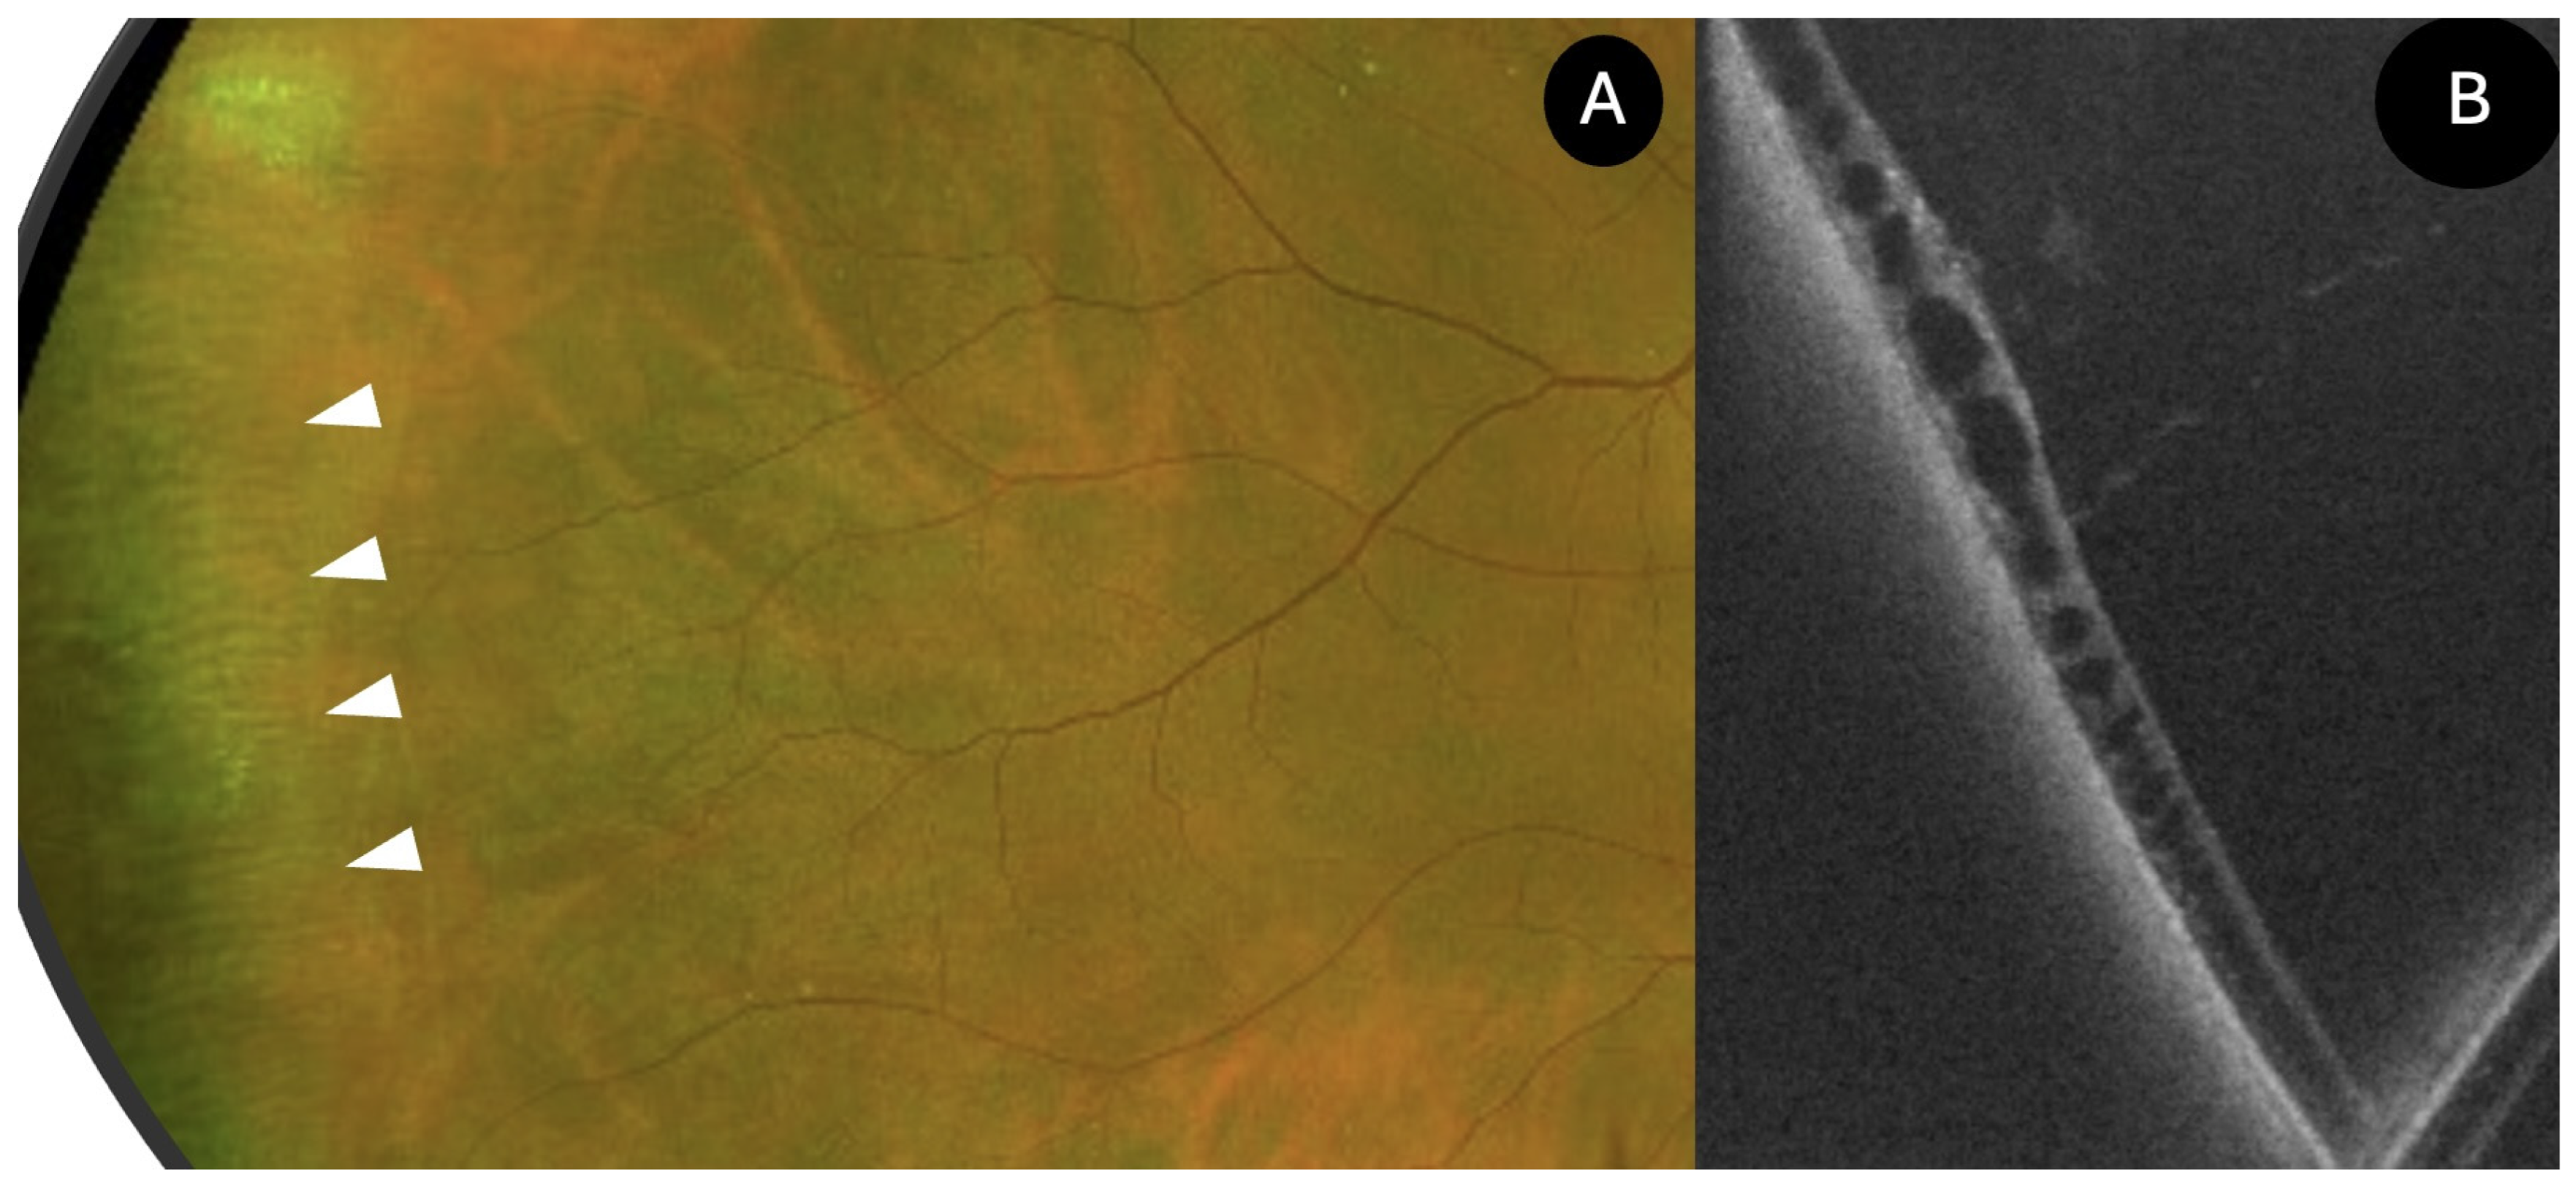

- White Without Pressure (N = 4)